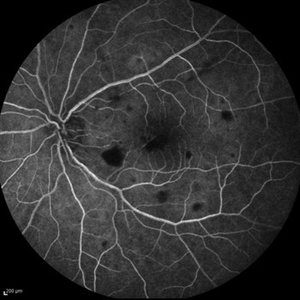

Best Disease Best DiseaseMar 9 2013 by Hamid Ahmadieh, MD FA and ICG Angiography of the left eye of a 49-year-old man with advanced Best disease. Photographer: Soodabeh Fooladin, Negah Eye Center, Tehran Imaging device: Heidelberg Spectralis Condition/keywords: Best disease, indocyanine green (ICG) angiography